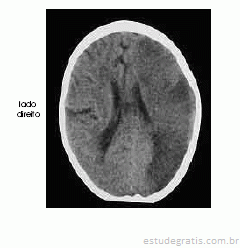

Um homem com 67 anos de idade, lavrador, deu entrada no pronto-socorro após ter sido encontrado, em sua casa, no chão e com dificuldade para falar e deambular. O paciente morava sozinho e os parentes não sabiam informar sobre uso de medicações ou patologias pregressas. Na avaliação, o neurologista identificou afasia mista, hemianopsia homônima direita e hemiparesia direita de predomínio braquifacial. Apesar de apresentar sonolência, o paciente ficava alerta ao chamado. A pressão arterial era de 180 mmHg × 90 mmHg. Foram solicitados exames complementares e de imagem, dos quais uma das imagens é reproduzida abaixo.